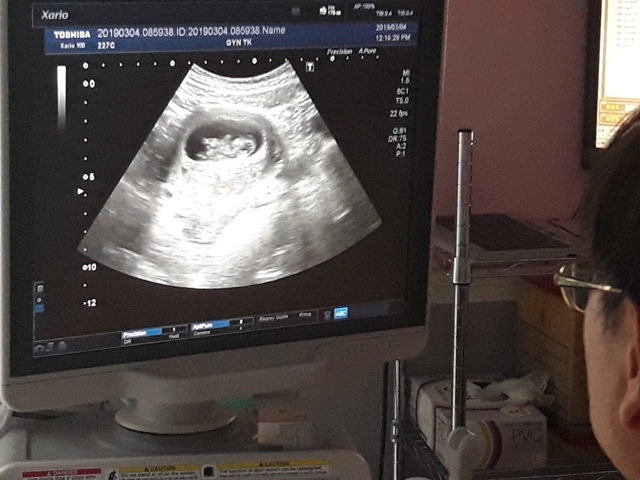

當小純進入診間看診時,我並沒有進去,因為小純說,有時男生不能進去,會被請出來。在外頭等待的我感到很緊張,不久之後,謢理人員請我進入診間,我嚇了一跳,想說發生什麼事了,進入之後,得知小純真的懷孕了,而且已懷了九星期又五天。看診的醫師說,驗孕棒第二條線淡淡的,沒想到胚胎照出來那麼大了,說Baby很健康。還說一閃一閃的是他的心跳,有頭、有手、有腳還有臍帶。小純後來說看了內心覺得很感動,才叫我一起進去看。

小純肚子裡的Baby超音波圖↓